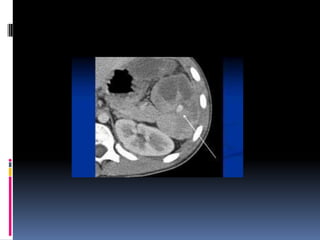

INJURIA PANCREÁTICA  Resultade la compresión de la glándula contra la columna vertebral  Manubrio de bicicleta  Clínica y laboratorio inicialmente inespecíficos

 Signos indirectosde lesión traumática  Agrandamiento difuso  Grasa peripancreática “sucia”  Líquido periglandular  Engrosamiento fascia pararrenal anterior